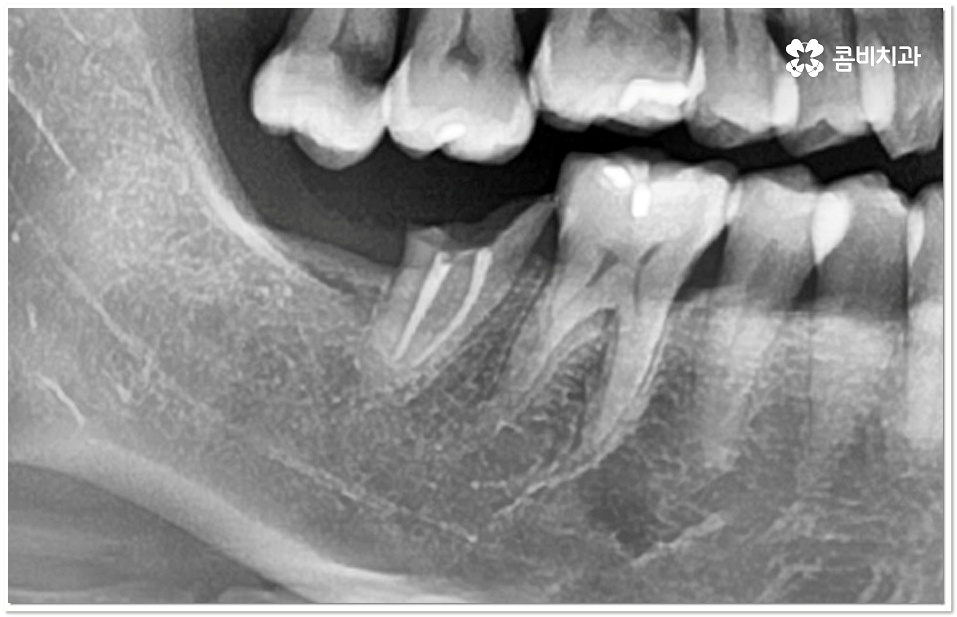

특히 20살 전후로는 사랑니 때문에 인접면 충치가 자주 발생할 수 있으니 신경써 주시길 권유드리고 있는데요. 어금니 뒤쪽으로 사랑니가 나올 때 비정상적으로 맹출이 되어 비스듬한 각도로 어금니와의 사이에 좁은 틈새를 만들게 되면 음식물 찌꺼기가 잘 끼고 쉽게 빠지지 않아 더욱 충치나 잇몸 염증이 유발되기 쉬우니 신경써서 관리해 주시길 바라고 있어요.

이 단계도 지나 치수까지 세균이 침투하게 되면 신경이 변성되고 통증이 심해지기 때문에 신경치료를 통해 이를 제거하고 내부에 충전재를 채워 밀봉한 뒤 전체를 덮어씌우는 크라운 치료를 해 주는데, 이와 같은 보존적 어금니 충치치료 로 자연 치아를 발치하지 않고 내구성을 좀 더 늘릴 수 있습니다.